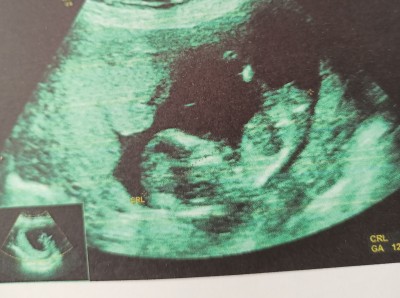

12+3 nub teorisine göre tahmin yapabilir misiniz?

Doktor 2 hafta sonra gel o zaman söylerim dedi. Nub ya da diğer teorilerden anlayan varsa yorum yapabilir mi?

Bebekte cinsel organ belli olmadan oradaki bölgenin duruş pozisyonuna göre fikir yürütüyorlar.

Erkek gibi geldi